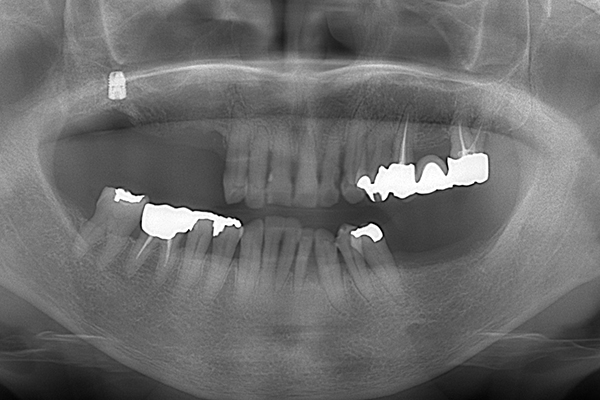

3.レントゲン診査

レントゲンで、顎の骨の厚みや、顎の関節の状態と位置を見ていきます。また、噛む力は強いのかなども診ることができます。 歯があれば、その状態も診査していきます。

上下の入れ歯が外れやすくなったということでいらっしゃいました。 顎の骨はしっかりしていましたので、精密な型取りさえすればしっかりした入れ歯がつくれると思いました。 また下には6本歯が残っていましたが、虫歯になっている歯もありました。 かぶせ物のなかで大きな虫歯があった歯があり、1本だけ残せない状態でした。

インプラント部以外にも歯周病が進行していましたので、歯周病の治療を行いました。 残念ながらインプラントと、1本の歯が残せなかったため抜歯を行いました。 その後、前歯の出っ張りを修正することと入れ歯の安定を図るため、残っている歯を全てかぶせ物にしていくことになりました。 写真中央は抜歯後に入れた治療用の入れ歯になります。 抜歯後歯ぐきが安定しましたら、入れ歯とかぶせ物の型取りを行いました。

治療内容 右上のボーンアンカードブリッジ(インプラントのブリッジ)部分がインプラント周囲炎になり、ぐらぐら揺れてきました。

そのため、インプラントを抜去した後、歯周病の治療と、予後不良の歯を抜歯して、義歯を作成していきました。